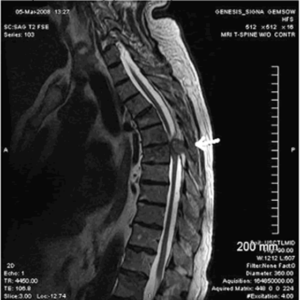

- МРТ. Информативный вид исследования, позволяющий судить о функциональном состоянии позвоночника, степени и характере его повреждения.

- магнитно-резонансная томография (МРТ) – самый надежный способ, можно увидеть изменение в мягких тканях, в том числе грыжу, оценить ее размеры, направление и риск развития тяжелых осложнений;

- Магнитно-резонансная томография (дает наиболее четкую картину спинного мозга, имеет сравнительные преимущества перед другими методами визуализации), на фото МРТ-снимок грыжи;